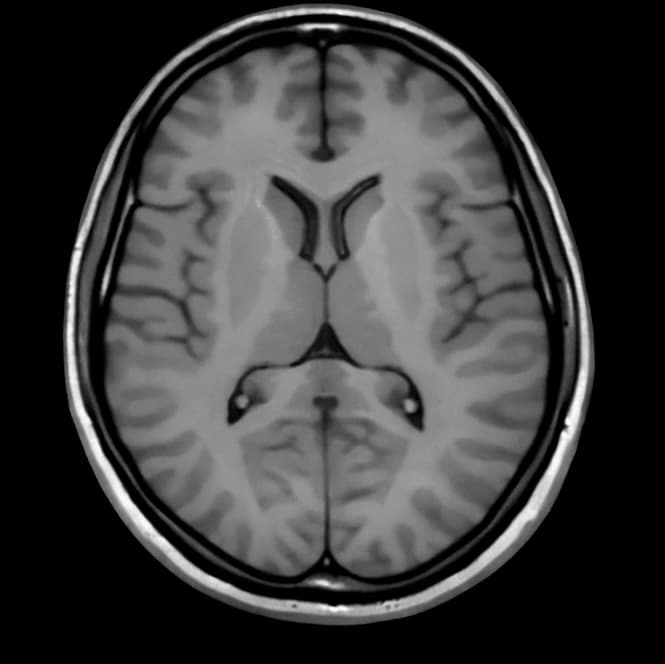

Image Enhancement Models

AI models designed to improve image quality by increasing resolution, reducing noise, and enhancing clarity.

Reconstruct higher-quality images from incomplete or low-quality inputs.

Enhancing Imaging Quality

Improve clarity and resolution of medical images.